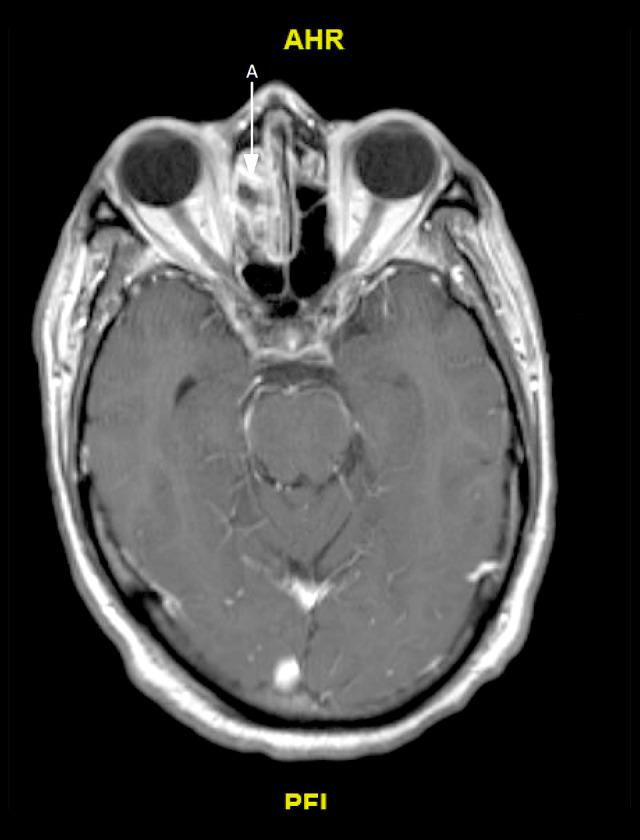

BACKGROUND We present a case of invasive sinusitis with rhinocerebral infection in a patient who had mild symptoms of COVID-19 infection and did not receive any immunosuppressive therapies. CASE REPORT A 49-year-old man with a history of uncontrolled diabetes presented to the hospital with multiple generalized tonic clonic seizures. He had recently been diagnosed with mild COVID-19 and was treated at home with supportive care only. He was found to have cerebritis in the right frontal lobe along with right fronto-ethmoid sinusitis. He underwent extensive testing with nasal endoscopy with gram stain and culture, cryptococcal studies, 1-3-Beta-D glucan, blood cultures, fungal CSF studies, Lyme disease, HIV, Fungitell assay, and galactomannan studies, which were all negative. He was started on i.v. antibacterial therapy with cefepime, vancomycin, and metronidazole along with amphotericin B. After 2 weeks, his repeat imaging revealed progression of cerebritis along with new early abscess. Given these findings, his antibiotics were changed to meropenem and the amphotericin B dose was increased. He was recommended debridement and sinus surgery but refused. During the course of treatment, he developed acute kidney injury and was switched to Posaconazole. Unfortunately, the patient decided to leave against medical advice 6 weeks into admission. He was advised to continue Posaconazole and levofloxacin but he could only afford levofloxacin. He was then recommended long-term levofloxacin. He has since recovered, with resolution of cerebritis noted in follow-up imaging 1 year later. CONCLUSIONS Our patient had mild COVID-19 infection and presented with secondary infective complications, which are usually associated with an immunocompromised state, despite receiving no immunosuppressives. It is imperative that all clinicians treating COVID-19 be watchful for fungal or bacterial co-infections in patients with active SARS-CoV-2 infection, even if the presenting symptoms are mild, particularly if other risk factors are present.

一名 49 岁男性,有未控制的糖尿病病史,因多发性全面强直阵挛发作到医院就诊。他最近被诊断为轻度 COVID-19,仅在家接受支持治疗。他被发现右额叶脑炎症伴有右额窦-筛窦炎。他接受了广泛的检查,包括鼻内镜革兰氏染色和培养、隐球菌研究、1-3-β-D 葡聚糖、血培养、真菌性 CSF 研究、莱姆病、HIV、Fungitell 检测和半乳甘露聚糖研究,结果均为阴性。他开始接受头孢吡肟、万古霉素和甲硝唑联合两性霉素 B 的静脉抗菌治疗。2 周后,他的重复影像学检查显示脑炎症进展,并出现新的早期脓肿。鉴于这些发现,他的抗生素改为美罗培南,并增加两性霉素 B 的剂量。他被建议行清创术和鼻窦手术,但被拒绝。在治疗过程中,他发生急性肾损伤,改为伏立康唑。不幸的是,患者在入院 6 周后决定出院。他被建议继续服用伏立康唑和左氧氟沙星,但他只能负担得起左氧氟沙星。然后建议他长期服用左氧氟沙星。1 年后的随访影像学检查显示脑炎症已消退,他已康复。